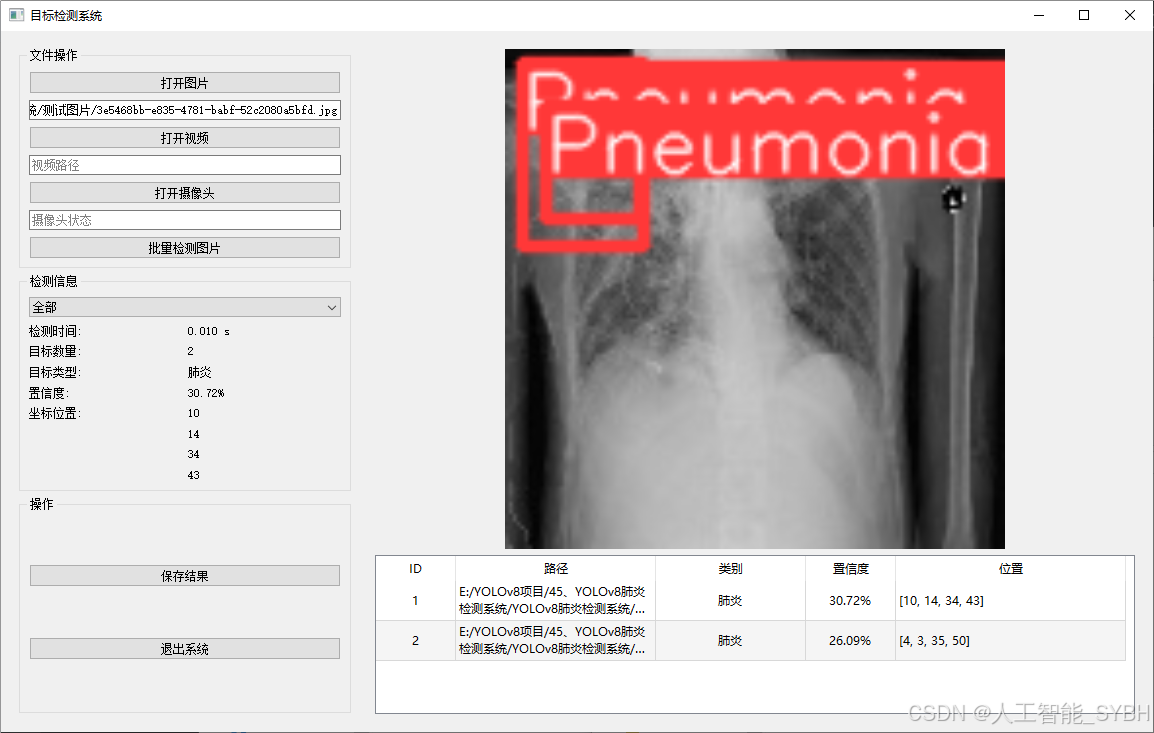

二、项目功能展示

系统功能

✅ 图片检测:可对单张图片进行检测,返回检测框及类别信息。

图片检测

该功能允许用户通过单张图片进行目标检测。输入一张图片后,YOLO模型会实时分析图像,识别出其中的目标,并在图像中框出检测到的目标,输出带有目标框的图像。批量图片检测